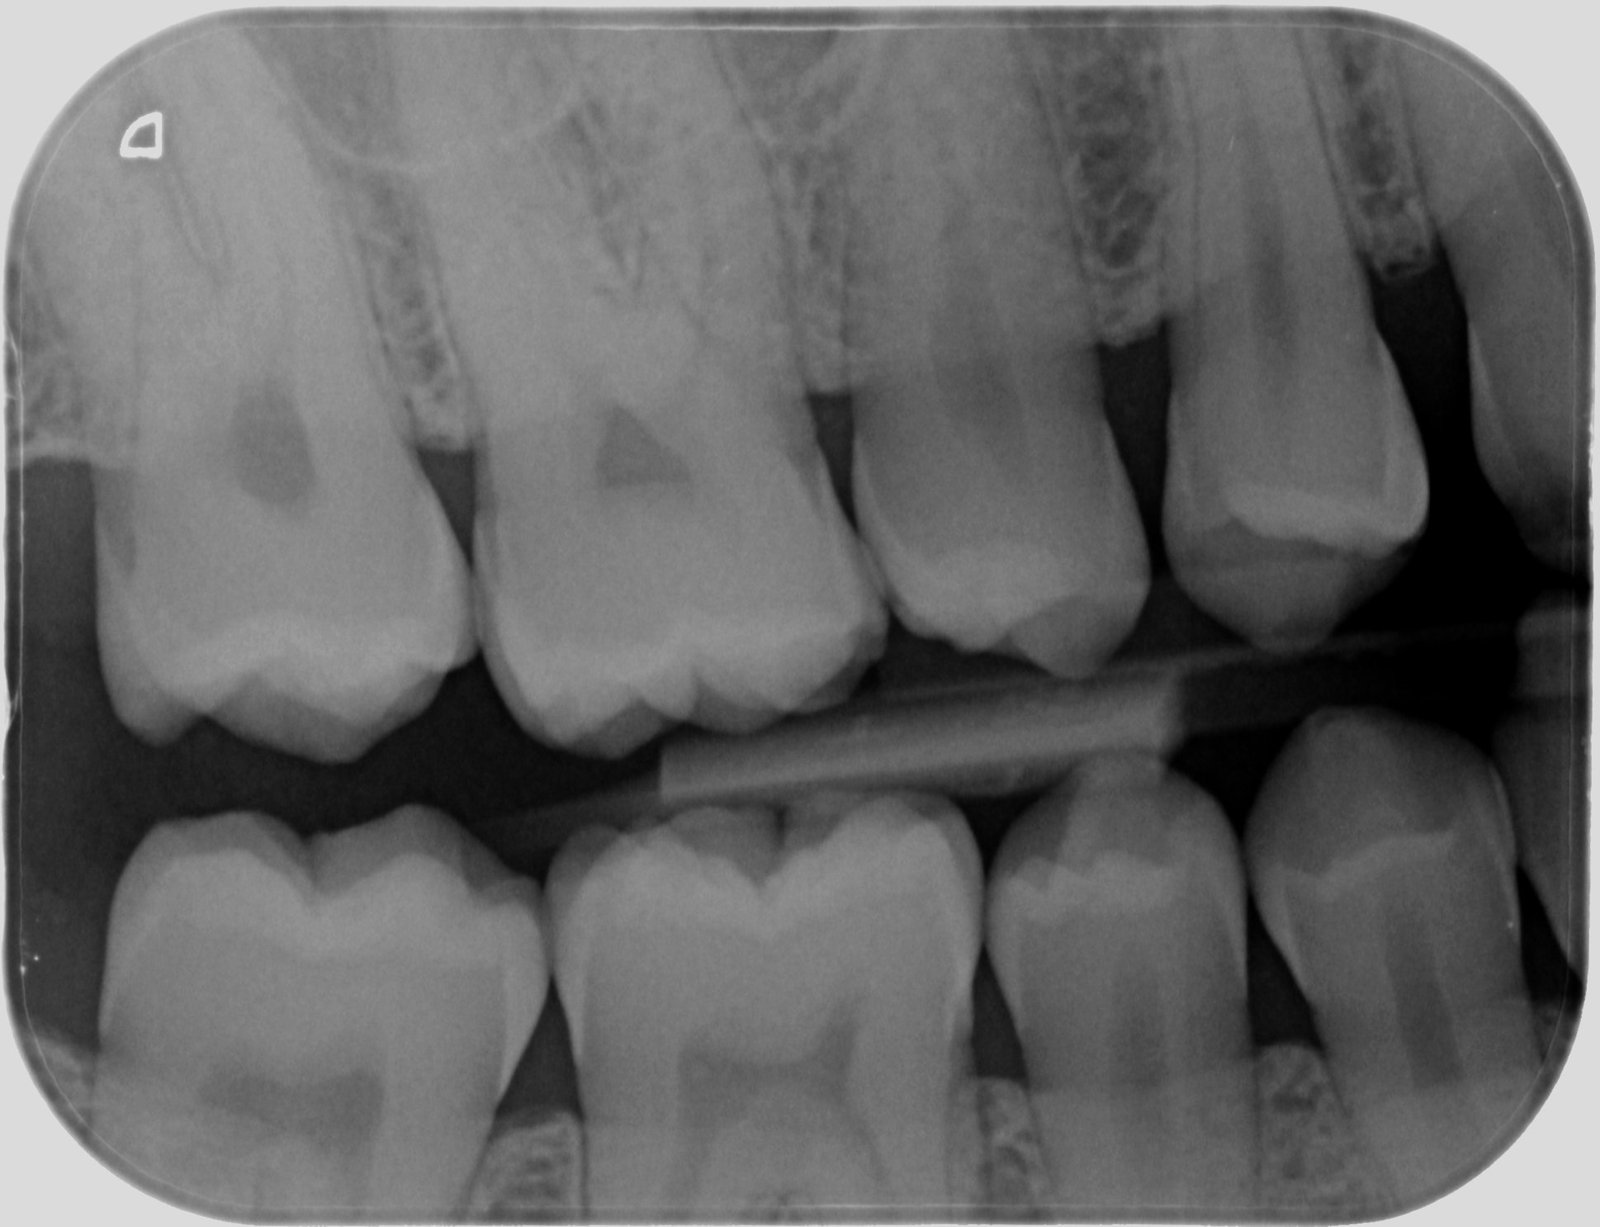

Radiografia digitală bite-wing

Radiografia bitewing este utilizată pentru a analiza zonele de contact dintre coroanele dinților posteriori vecini sau pentru a evalua conturul osului alveolar în regiunea respectivă. Aceasta capturează simultan coroanele dinților superiori și inferiori pe aceeași imagine. Principalul său obiectiv este identificarea cariilor interdentare, precum și a celor ascunse sub plombe sau lucrări dentare, facilitând astfel un diagnostic precis pentru tratamentele stomatologice.